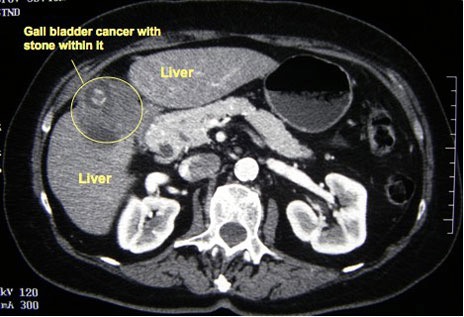

Spiral CT scan probably gives the best estimate of the extent of disease. However, MRI scanning gives equally high-resolution images, with the additional benefit of providing an MRCP. CT and MR usually give adequate information about the localblood vessels, and hepatic angiography is rarely indicated.

CT scan picture showing a cancer that has arisen from the gall bladder. A gallstone can also be seen -